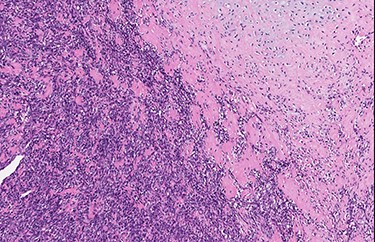

Low-power view of the lesion showing central ossification (H&E).

Abrupt transition from small cell component to well differentiated cartilaginous area (H&E, high power view).